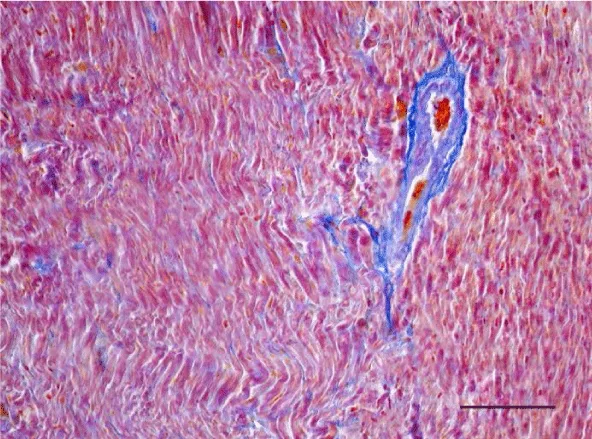

Mallory’s trichrome stain in 2-week-old animals revealed a scarce amount of fine collagen fibers in the walls of the two ventricles. Very few thin and quite short connective tissue fibers were noted in the interstitial space of the left ventricle. More collagen fibers were situated predominantly in the perivascular zone and in the walls of the blood vessels and were stained in an intensive blue color; we noted a slight tendency for collagen fibers to grow from the perivascular zone towards the interstitial space (Figures 3,4).